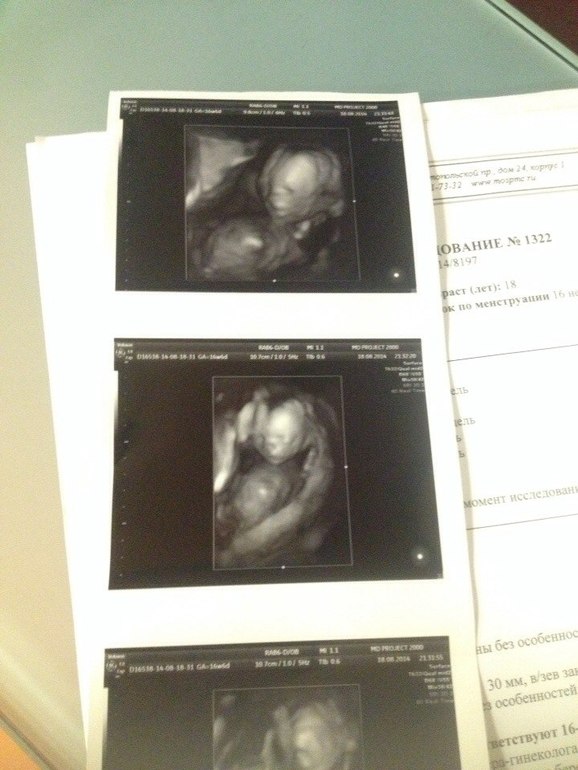

Но когда я зашла, и когда она первым же прикосновением датчика подтвердила пол, который мне сказали еще при хромосомном анализе, когда она спокойно все объясняла, где ножки, где ручки, я растаяла.

Сын так же сладко зевнул и помахал нам ручками.

В общем все у нас хорошо, слава Б-гу. Развит на свои 16-17 недель. Как раз по менструации вчера ему было 16 и 6, а по узи ранних сроков 16 и 3. Осталось в 20 недель еще убедится в том, что сердце здорово и можно слегка выдохнуть.

фотки под катом,